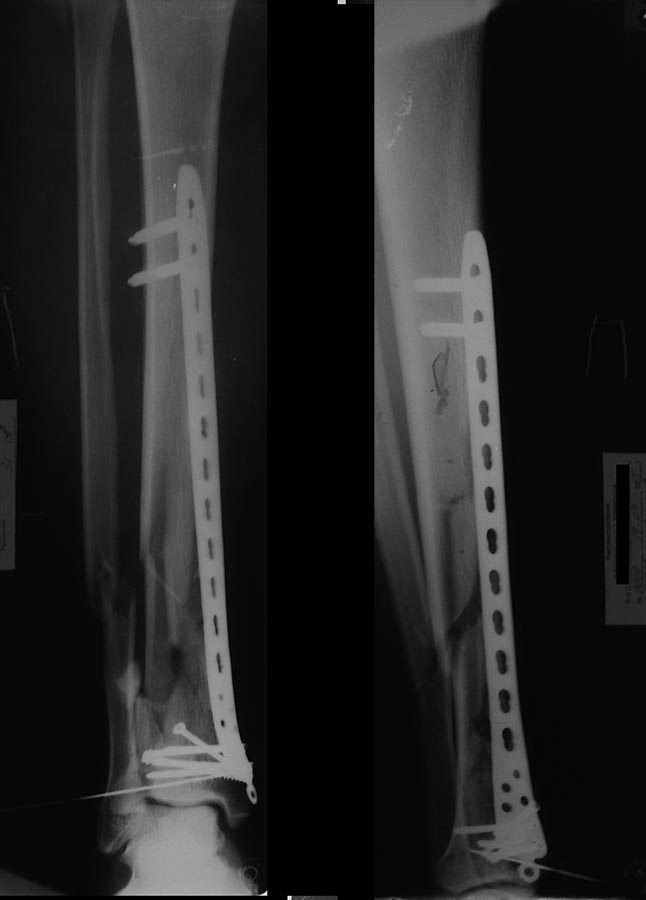

Доброго времени суток! Может как-то так? Закрытая репозиция, мостовидная фиксация. Случаю 4 года, функциональный результат хороший(прошу прощения за качество снимков)

Уважаемый Кирилл предоставил отличный послеоперационный снимок. Мой хуже, конечно. Но без ЭОП и через два разреза вышло вот так.

Там ещё вверху винт добавил и в эпифизе один спонгиозный с фиксацией костного фрагмента и аутотрансплантата.